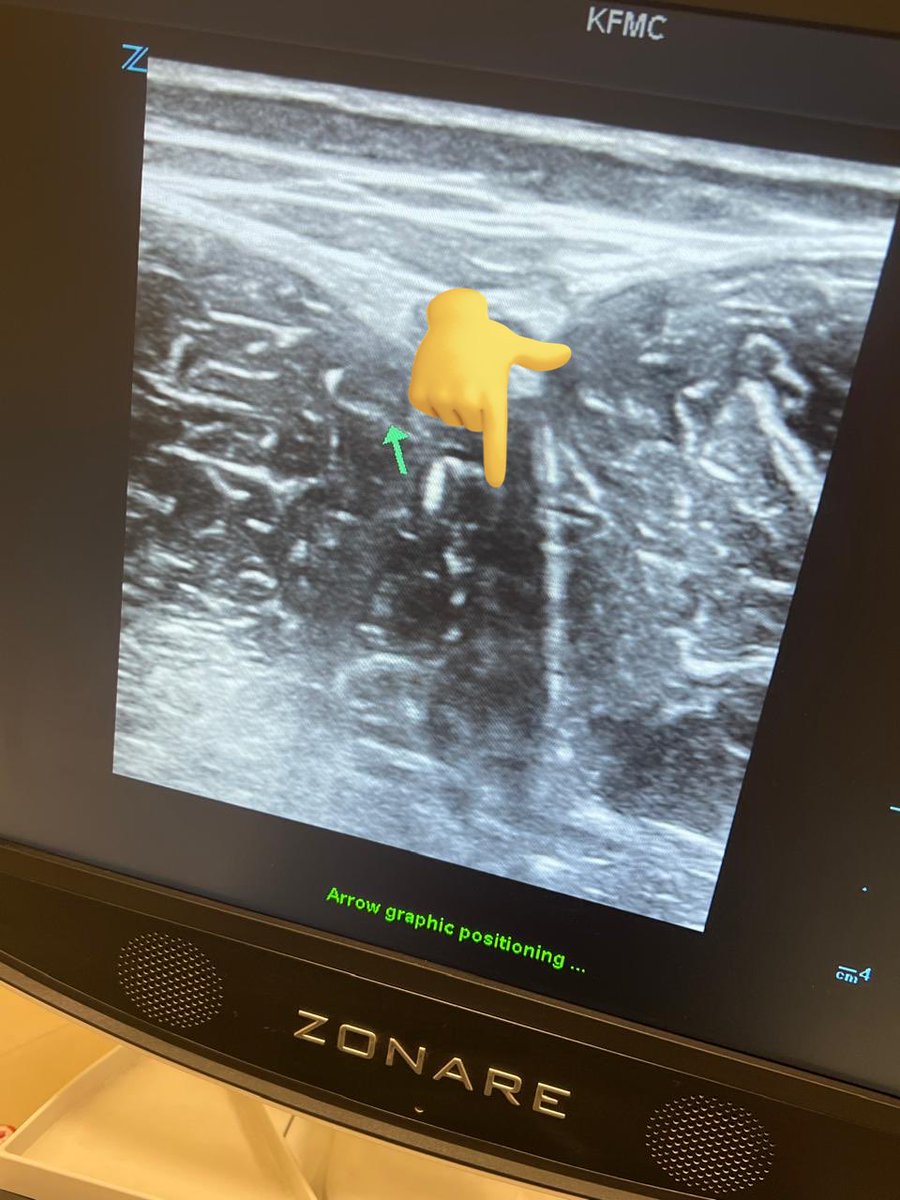

بعد التقييم السريري 🛏ضروري تشوف الإصابة تحت الأشعة🩻: وأسرع شي هو الالتراساوند ولكن تعتمد على مهارة المستخدم فيها

هذي صورة إصابتي بالالتراساوند/ السونار

اغلب الاصابة بالbiceps

وهي من الدرجة الثانية.😅